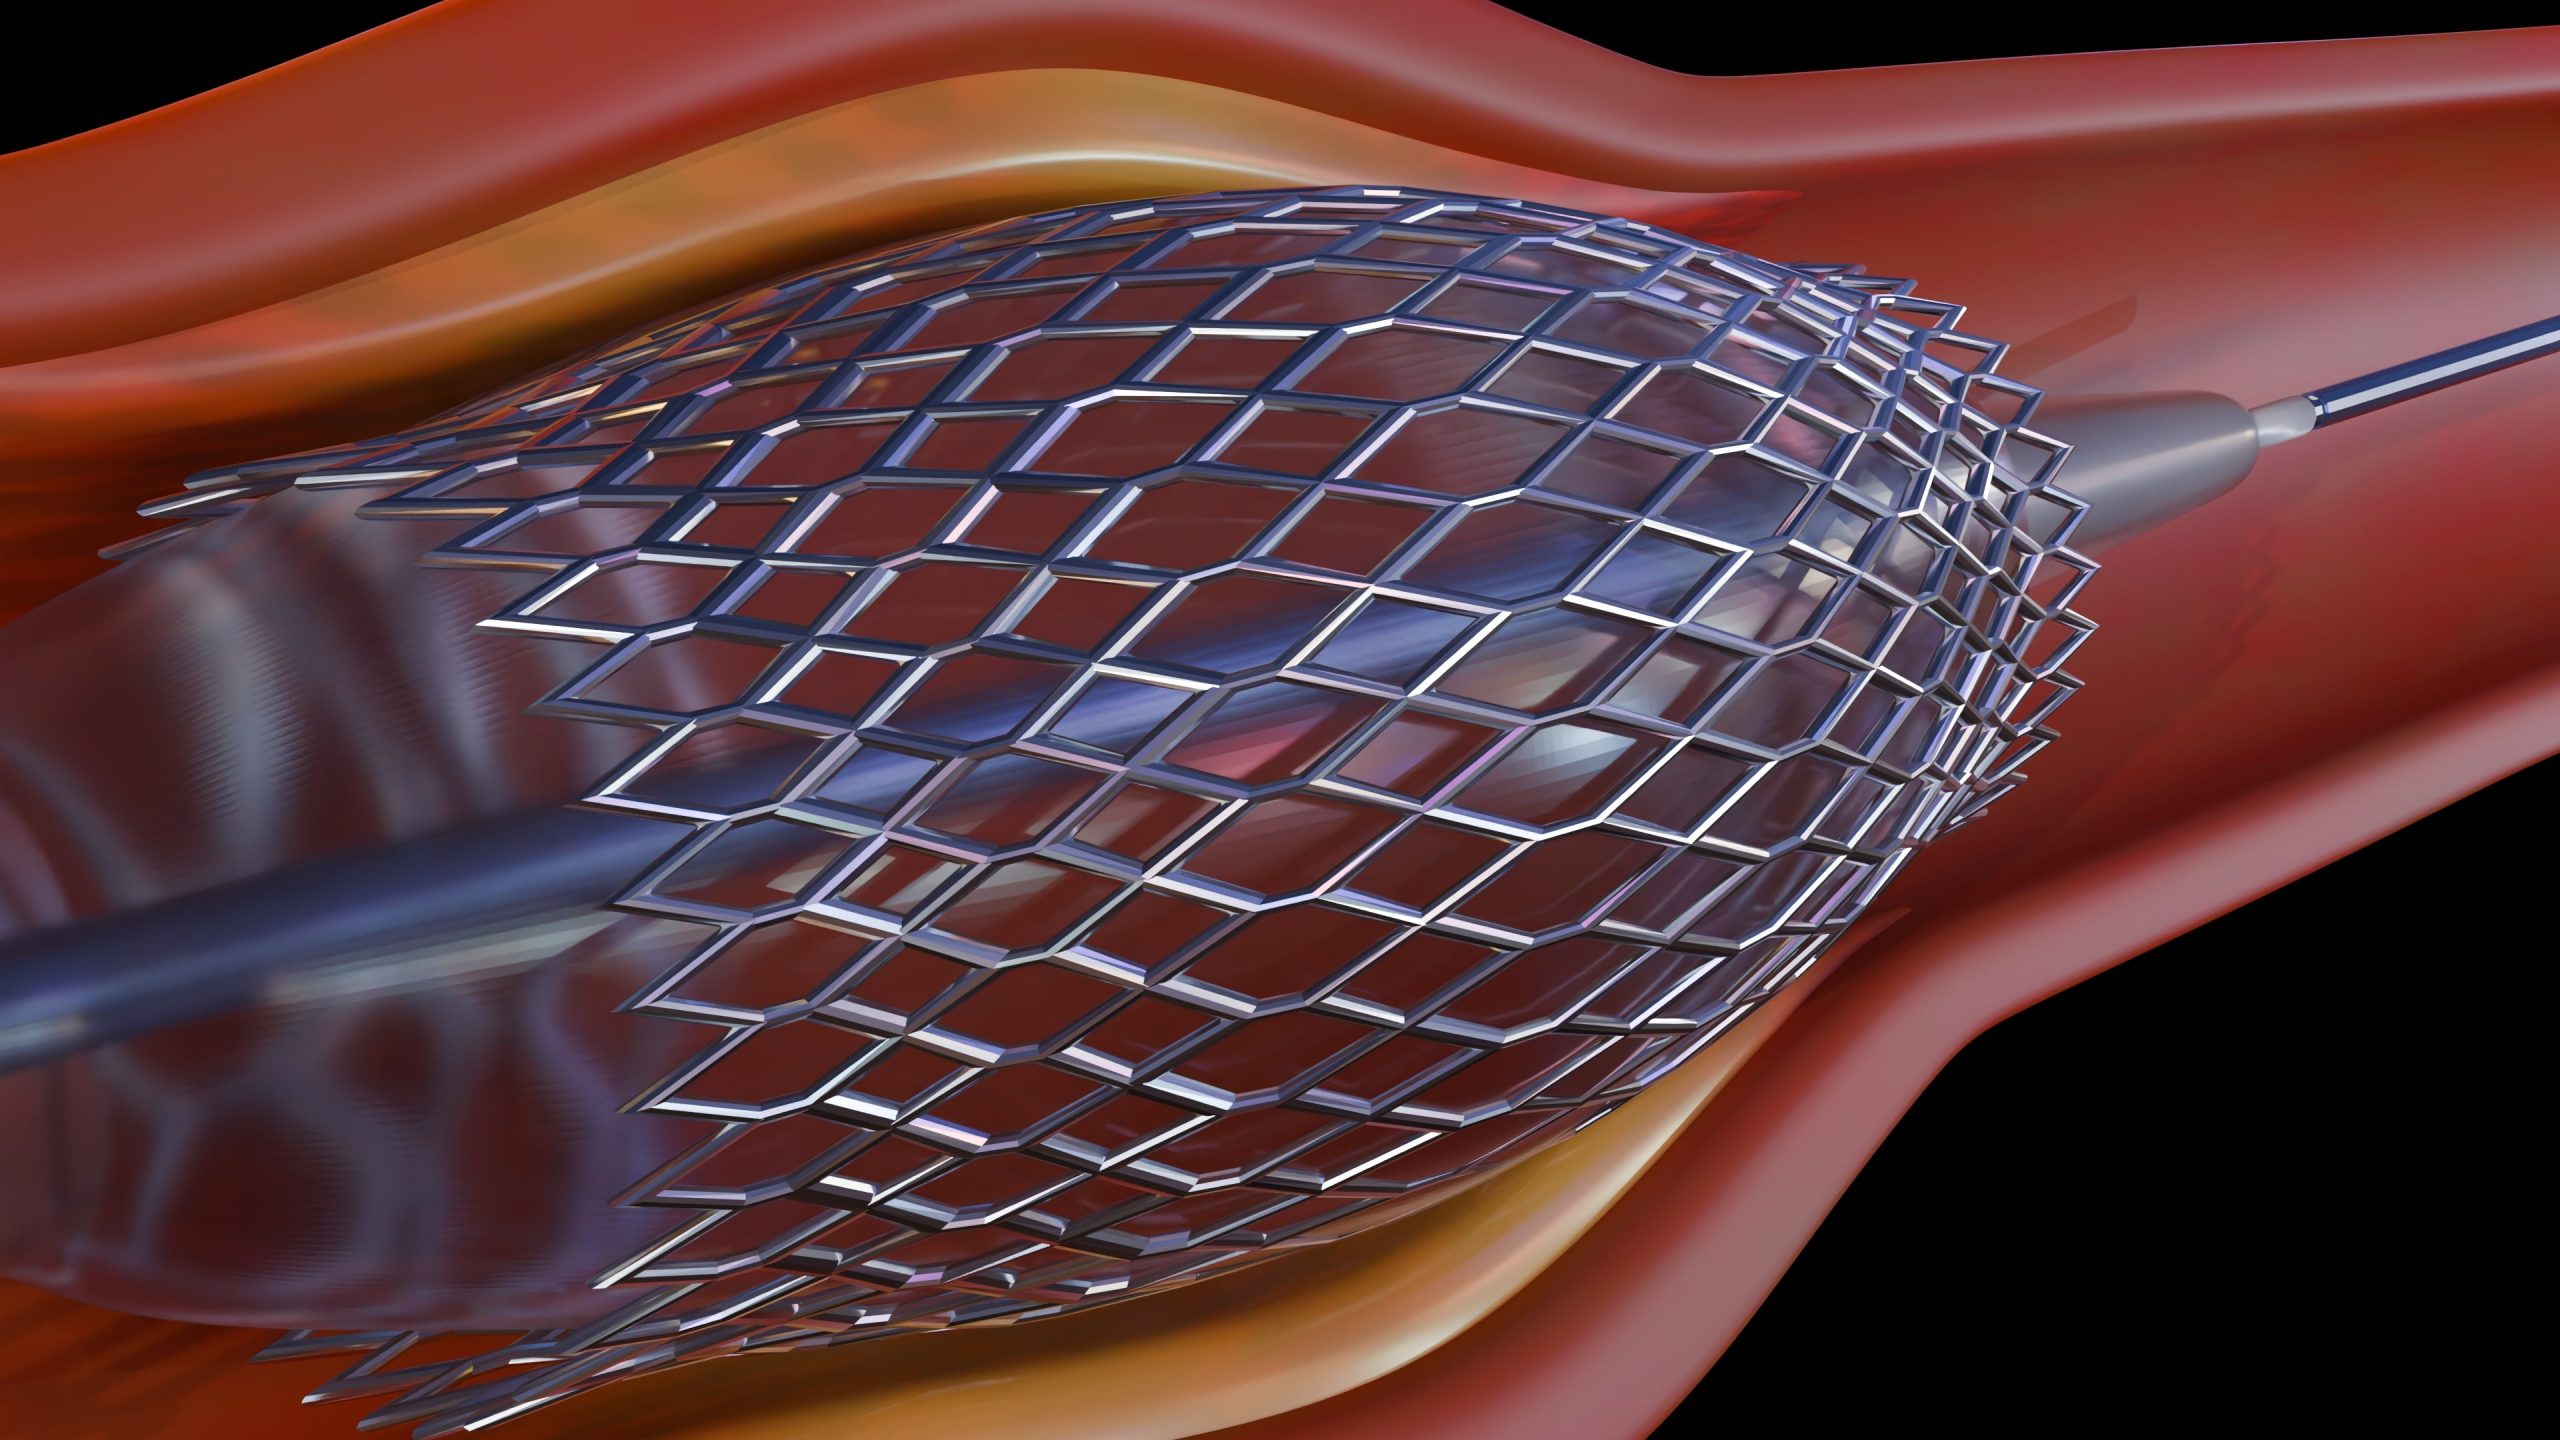

Saving 50,000 lives annually by developing next-generation Heart Valves

Ensuring surgical success with sterile tools designed for pediatric heart procedures.